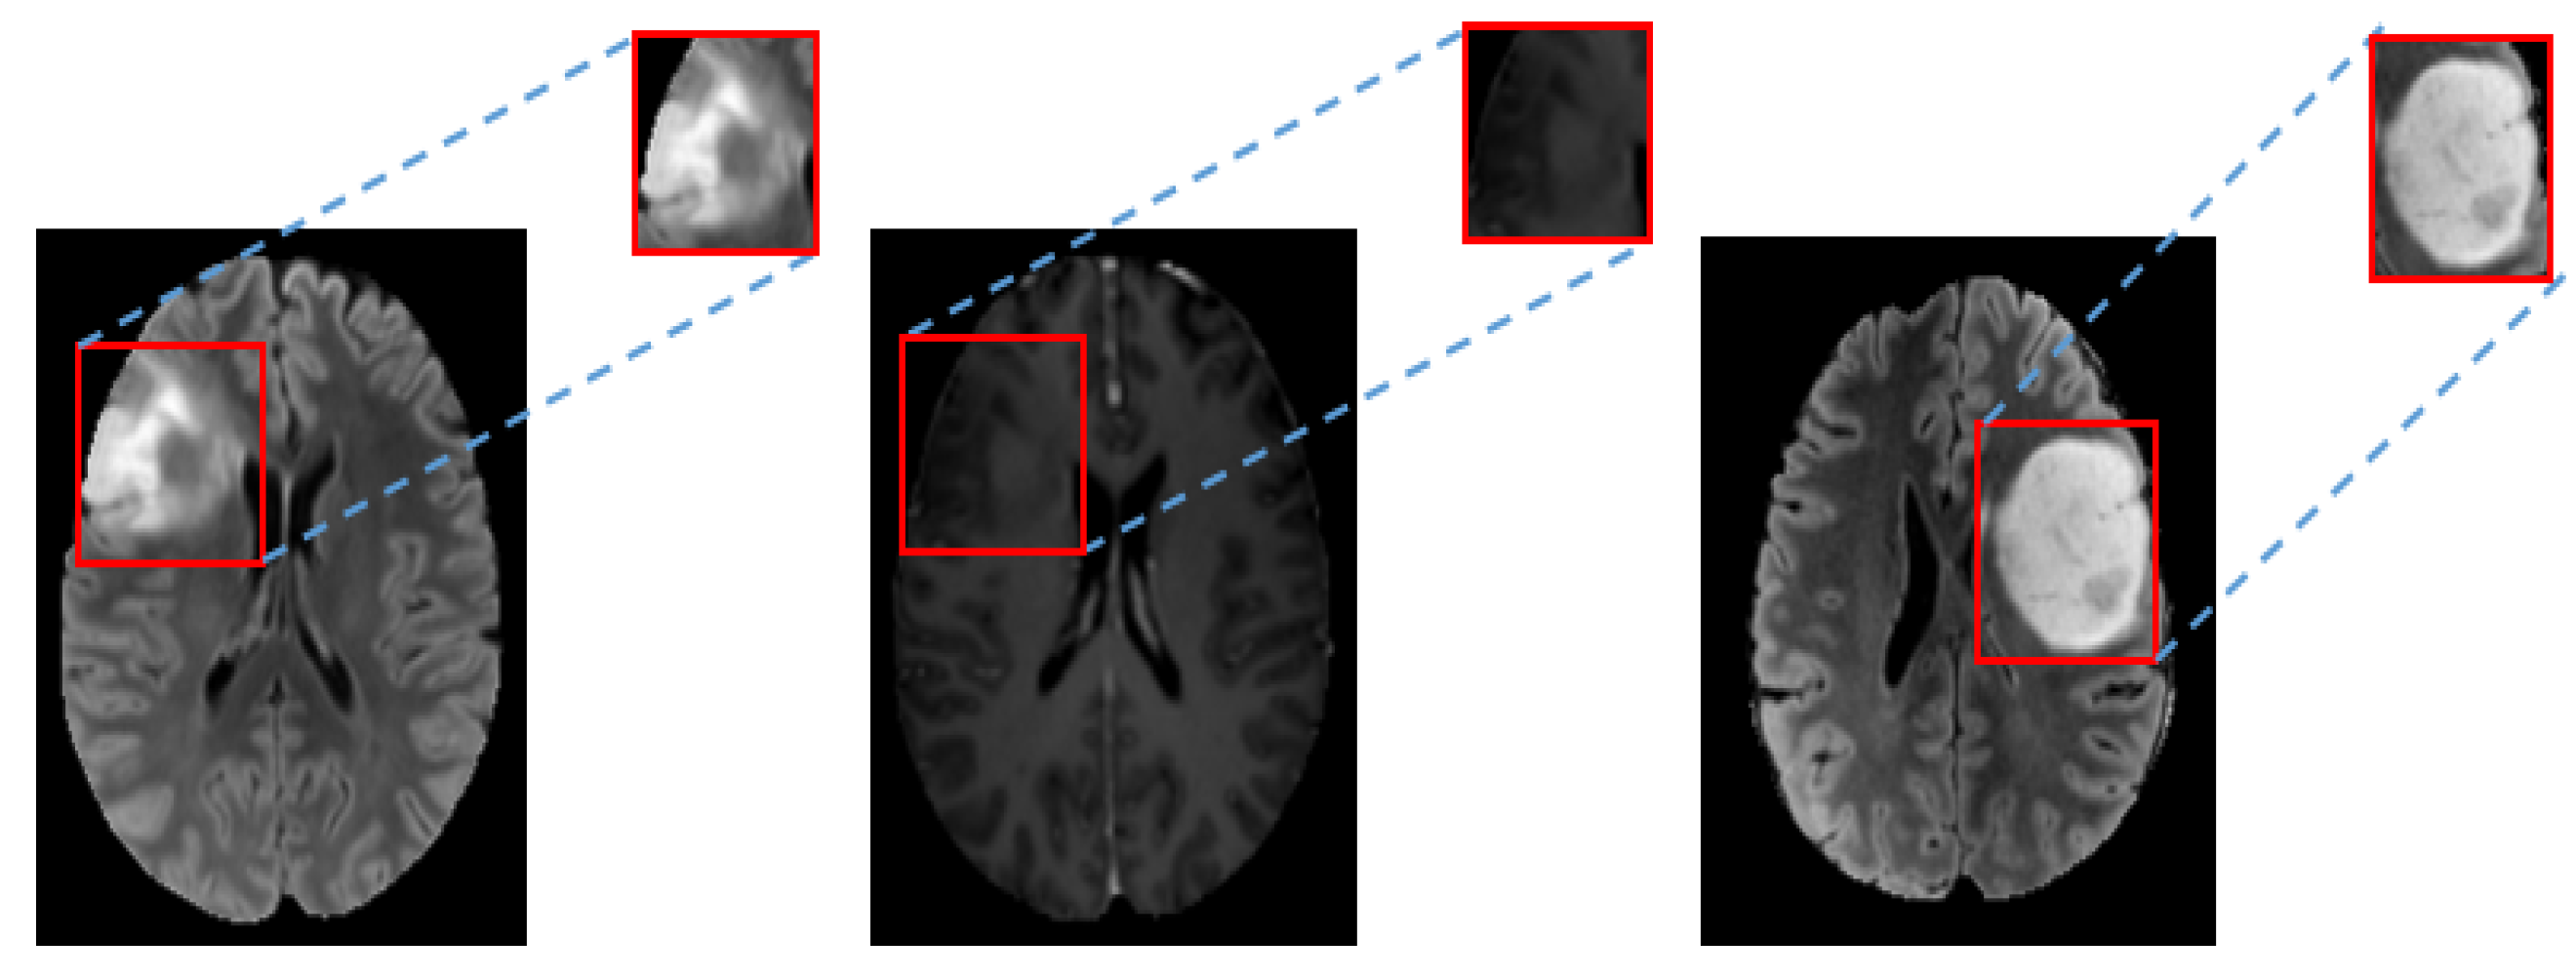

A tight bounding box of rectangular shape was used by allocating the tumor region on each image. Images of tumor regions were then used as the input for more efficient tumor feature learning. Figure 5 shows an example of tumor regions used for feature learning. After that, all tumor regions were normalized to 64 × 64 pixels.

Figure 5.

Example of allocated tumor regions by rectangular bounding boxes for tumor feature learning. Left to Right: FLAIR, T1ce and FLAIR.